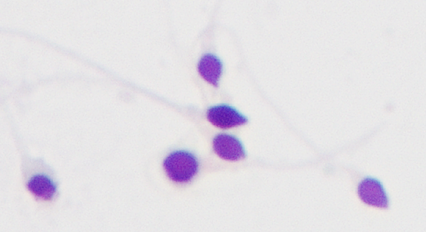

一条精子,全长50μm(1cm=10000μm),由三大主要部分组成:头部、颈部和尾部。

一个健康的高颜值精子,应该由一个完美、光滑的椭圆形头部和一条长而飘逸的尾部组成。

头部畸形精子

圆头精子

多头精子

精子头部顶体区空泡

精子头部顶体区大于头部的70%。

精子头部顶体区小于头部的40%